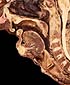

Faringe - Laringe